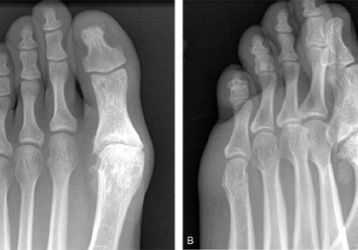

Артроз плюснефалангового сустава: причины возникновения, способы диагностики и лечения

Артроз плюснефалангового сустава, как диагностировать и лечить заболевание. Основные симптомы и признаки недуга. Перечень медикаментов для терапии.

Особенности диагностики и лечения остеоартроза суставов стопы

Диагностика симптомов остеоартроза стопы. Причины заболевания. Медикаментозные и хирургические способы лечения мелких суставов.